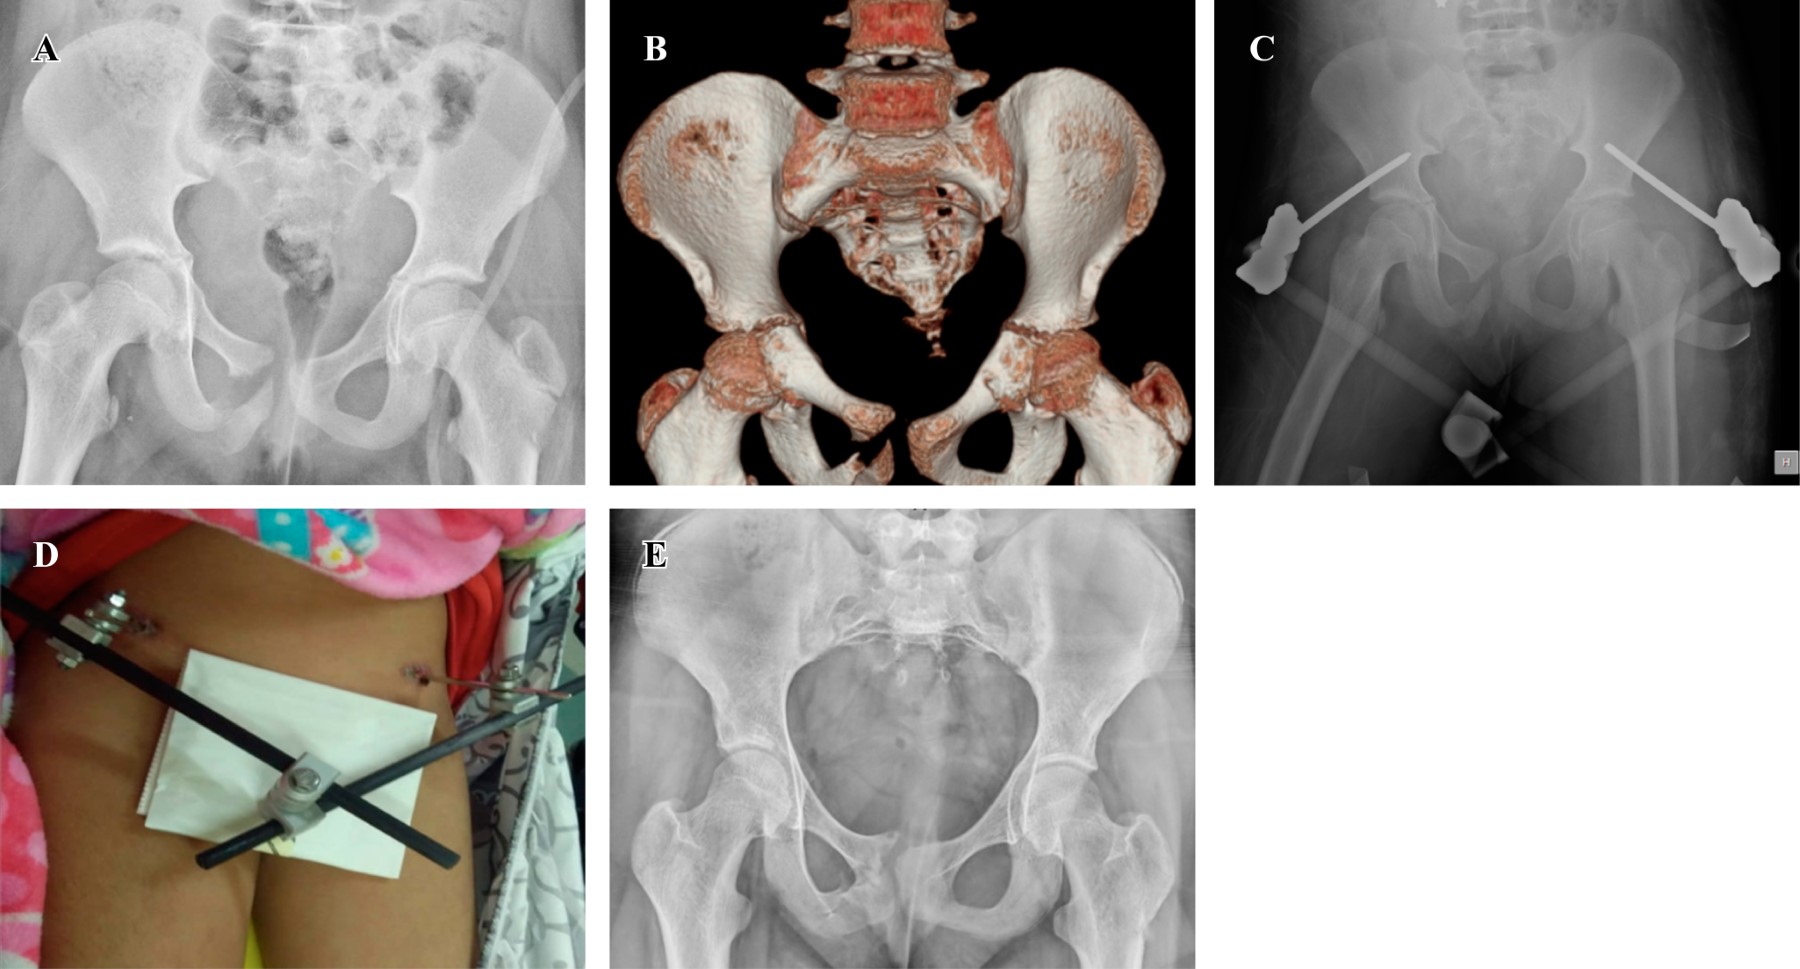

Figure 2

Clinical and functional evaluation of pediatric patients with pelvic fracture treated in a third level Hospital